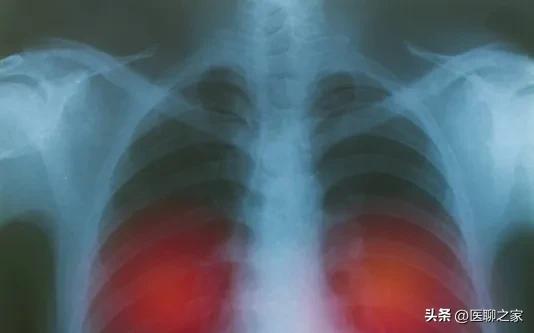

6、肺癌筛查——胸片、胸部CT

对健康正常人群进行早期肺部筛查是预防肺癌的最主要和最有效的方法。如通过X光、CT检查,尤其是低剂量螺旋CT在肺癌早期的诊断中有非常重要的作用,是目前最常用的肺癌早期筛查手段,可以发现肺内是否有可疑的病变。